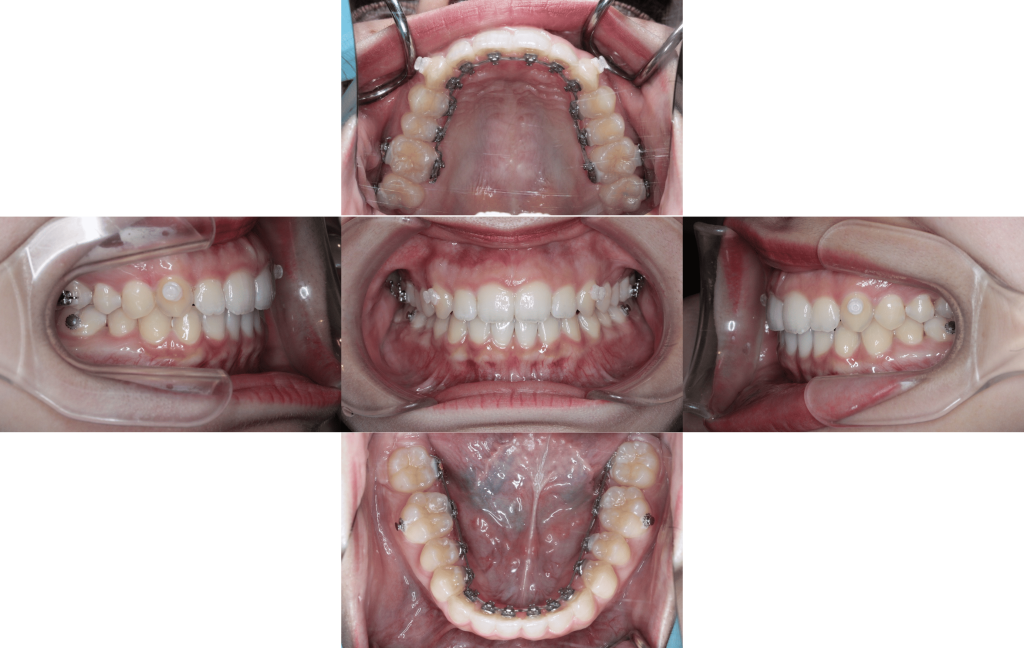

約1年後